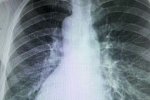

男子五脏六腑颠倒:温州41岁男子张先生体内五脏六腑的位置与常人相反,是罕见的镜面人,温州附二医为这位镜面人做完腹腔镜直肠癌切除手术,因为五脏六腑颠倒,手术难度很大。

东莞现镜面人,五脏六腑长的位置和一般人相反,正常人的心脏、脾脏在左侧,肝脏在右侧。但日前,东莞市第八人民医院收治的一名病人正好相反,他的心脏、脾脏在右边,肝脏在左边。

东莞现镜面人,因左下腹疼痛难忍,到医院检查不出什么毛病,后来还是医生突然脑洞大开,发现这位患者竟是罕见的“镜面人”,五脏六腑全长反了。